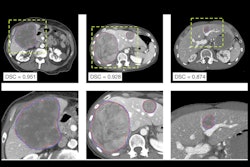

The research team aimed to test seven machine-learning models with 13 feature-selection techniques in predicting clinical outcomes following treatment of patients with advanced HCC with atezolizumab and bevacizumab as combination immunotherapy, using radiomic features from CT imaging performed prior to treatment.

Integrated predictive models incorporating radiomics and clinical features were then used to stratify the patients across two different cohorts, one in the U.K. and the other in France.

After analysis, the results showed that the radiomics-based machine-learning models, when coupled with deep-learning autosegmentation, could outperform established clinical benchmark variables in predicting clinical outcomes. Furthermore, not only was the integrated radiomic-clinical model able to predict responses to immune checkpoint inhibitors, it was also better at predicting overall survival and progression-free survival than known clinical predictors. The predictive ability of the model was consistent across both cohorts.